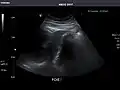

Renal ultrasonography

Ultrasound scan of a kidney (right side)

Ultrasonography of the kidneys is essential in the diagnosis and management of kidney-related diseases. The kidneys are easily examined, and most pathological changes in the kidneys are distinguishable with ultrasound.[7]

Kidneys: Right and left kidneys measure 11.5 cm and 12 cm in length respectively. No hydronephrosis. Small left lower pole kidney cyst.